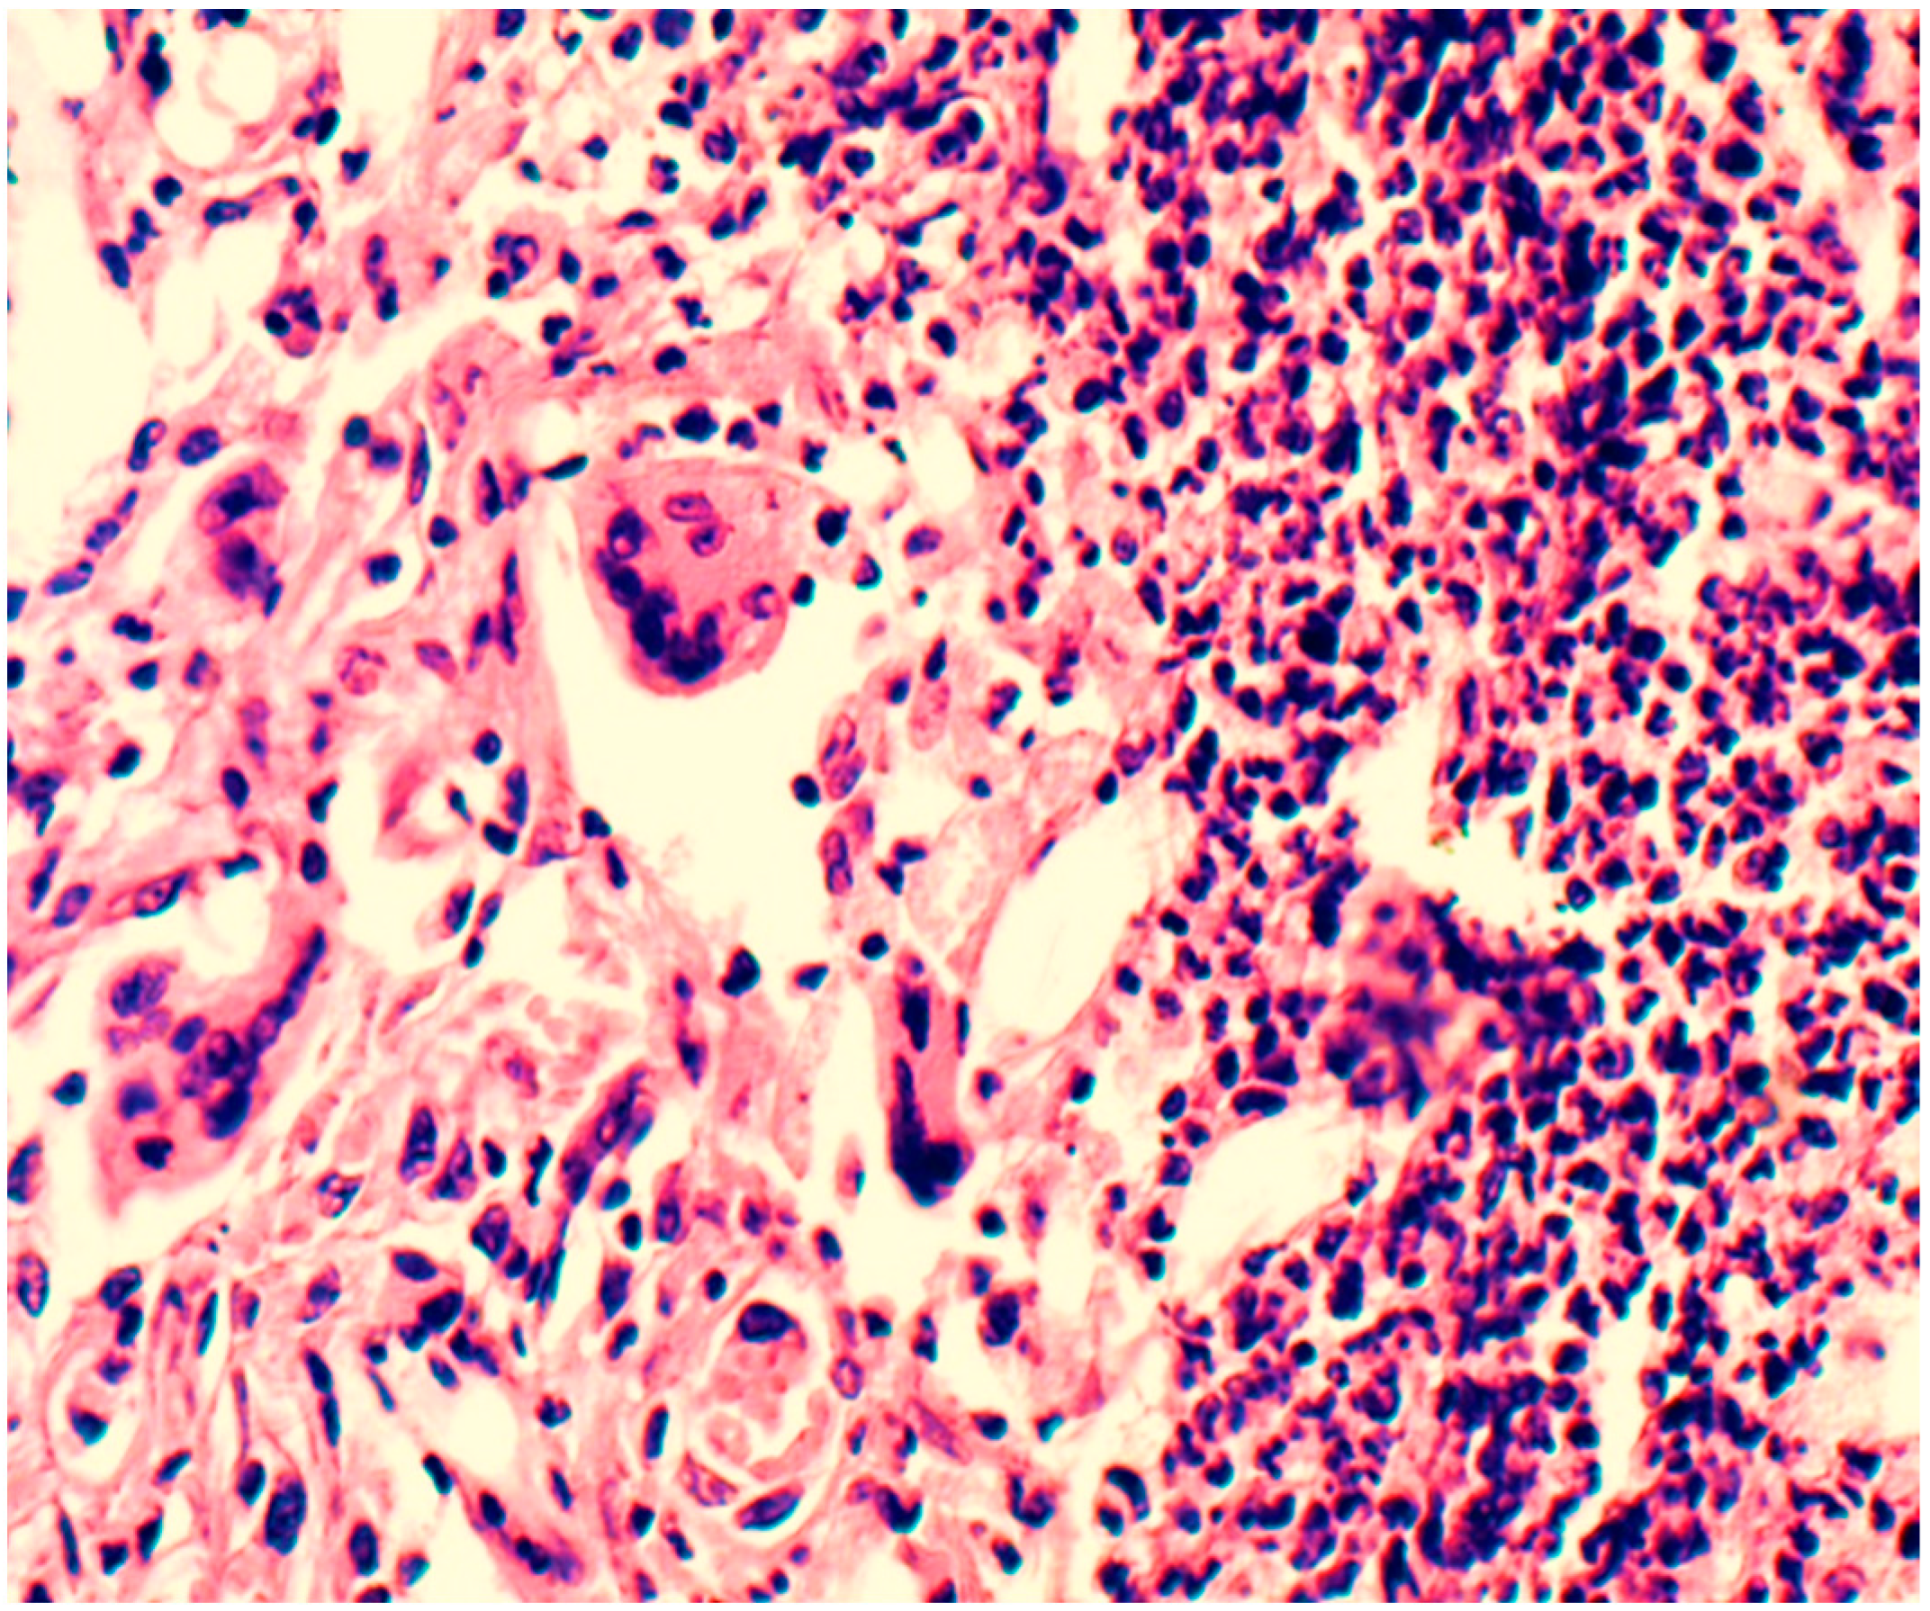

- Using morphometry, it was established that this polymer begins to biotransform one month after implantation, when the transformation of the synthetic matrix begins under the influence of physicochemical degradation processes and biological transformation processes, accompanied by the absorption of released biopolymer chains by macrophages. Before this period, an inflammatory infiltrate was formed along the border with the material, which after one month, due to biotransformation processes, moved into the depth of the polymer matrix, increasing the area of inflammation. In terms of qualitative composition, in the first two weeks, the inflammatory infiltrate was mainly represented by macrophages, leukocytes, and lymphocytes. After one month, the number of inflammatory cells decreased, especially macrophages—they were partially replaced by fibrocytes and fibroblasts. Subsequently, the composition of the infiltrate changed little.

- In vitro, the polymer biodegradation began from week 2. According to the spectrometry data, this process was not linear; in the first two months, the Mw and Mn values remained virtually unchanged from week 2. At three months, the Mw value was 14.4% less than the initial value. The degradation process in tissues, according to the spectrometry data during three months of implantation, remained unclear in the course of this research. The Mw and Mn values for the biopolymer from tissues after three months of implantation were greater than these values for the polymer degrading in vitro at three months and even at 0 months. Complex metabolic processes in tissues during inflammation and involving various chemical agents can explain this contradiction. The data obtained can serve as a basis for further, more detailed study of the physical parameters of polymer degradation in tissues and in vitro. However, the in vitro results confirm a delayed degradation period of at least a month, which was confirmed by the histological study of peri-implantation tissues. According to histological studies, cell migration into the biopolymer began in the first month of the experiment. This is somewhat earlier than the polymer degradation processes in vitro. As described above, during this period, macrophages were predominantly in direct contact with the biopolymer. Based on this, it can be assumed that macrophages are active participants in the biotransformation process and absorb polymer chains of the biopolymer as a result of phagocytosis. This assumption can also serve as a subject for future studies to determine the molecular weight of polymer chains formed during degradation and the ability of macrophages to absorb these chains, determining the rate of biopolymer biotransformation.